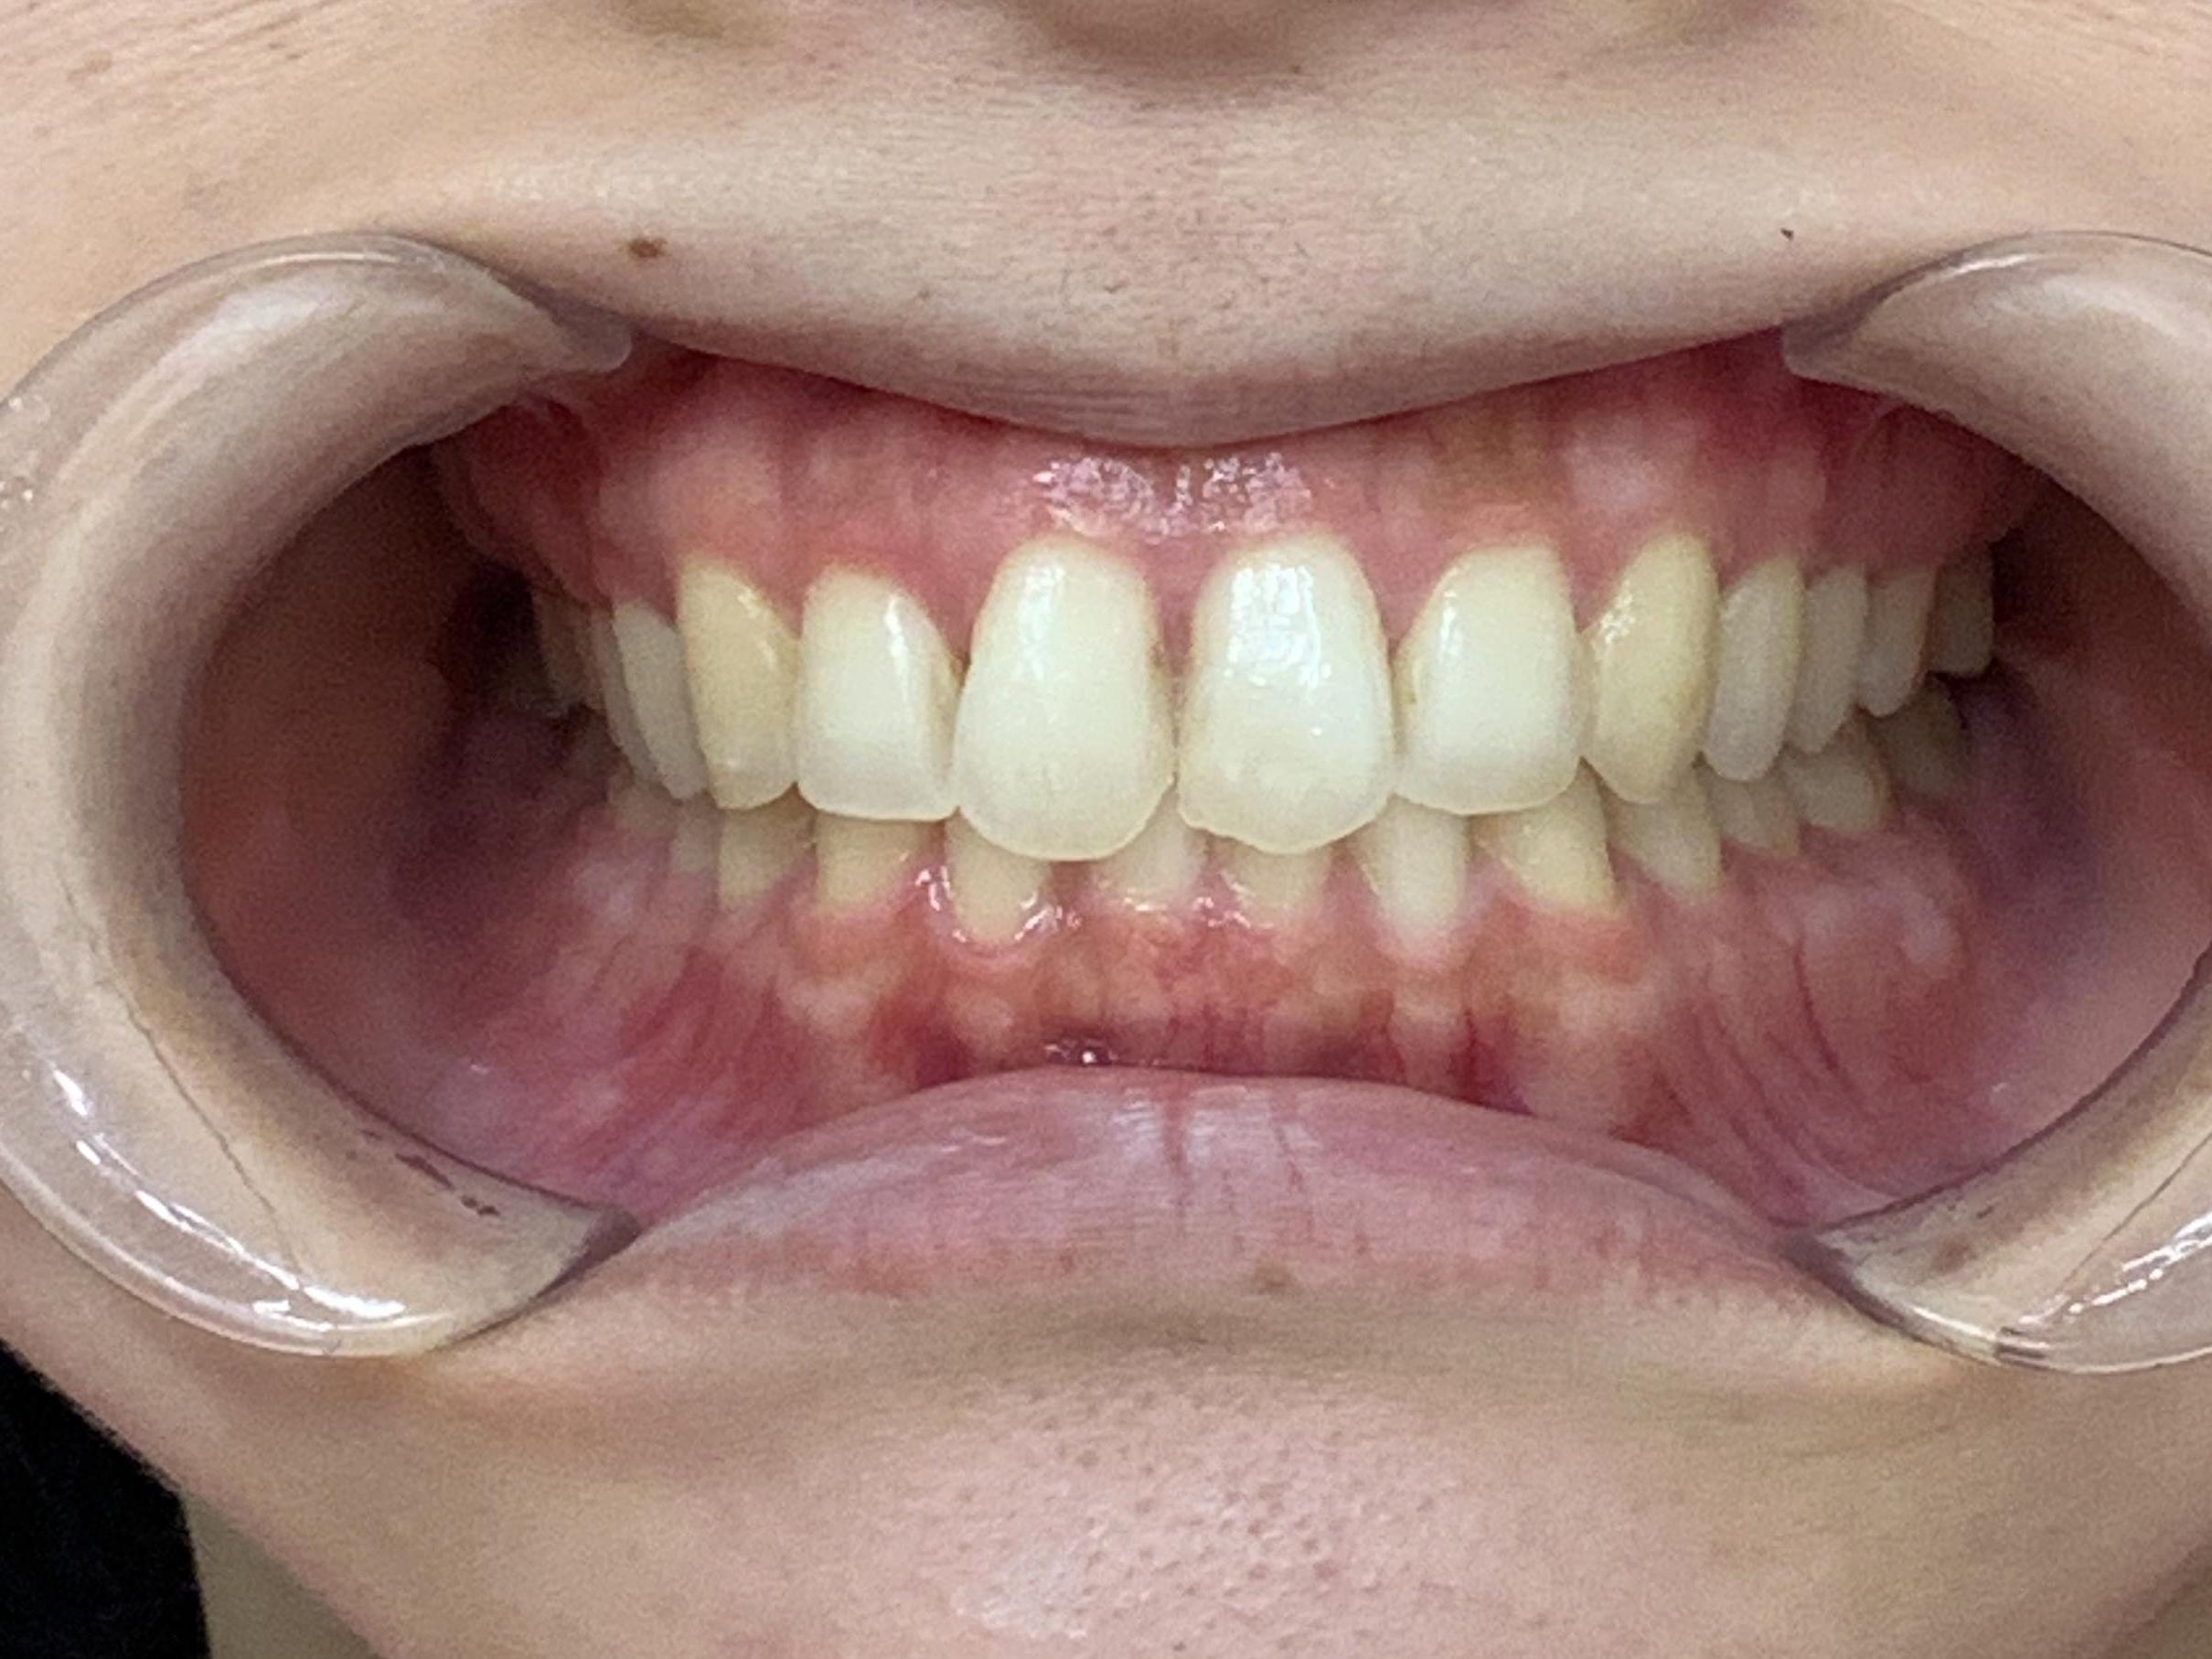

途中半年ほど中断期間がありましたが、上下前歯はきれいな歯並びになりました。

横から見た時の出っ歯感もなくなり、噛み合わせも問題なく、経過は順調です。

患者様からは「歯の捻れが改善されて、気にせず笑えるようになりました」と大変喜んでいただけました。